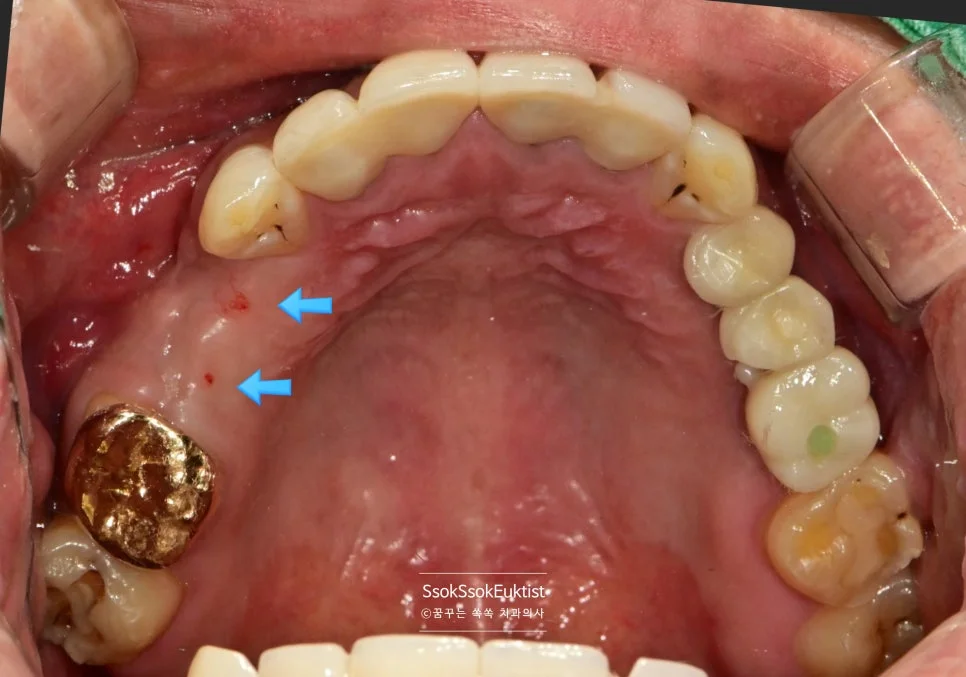

치료 전 정면 구내사진 — 다수의 치아 문제가 보이는 상태

그런데 2번의 임플란트를 한번 보면 뭔가 잇몸이 부자연스러운 것을 볼 수 있는데요.

임플란트 주변에 뼈가 다 녹아내리고 그 바깥에 잇몸까지 혈류를 받지 못해 점점 괴사하고 있는 모양새입니다.

임플란트 식립한 자리 주변이 예쁘게 잇몸으로 아문 것을 볼 수 있습니다.

2번 자리의 잇몸을 보면 처음보다는 훨씬 건강한 잇몸이 된 것을 볼 수 있는데요. 한 달 후 체크 약속에서도

1개월 후 경과 관찰 — 2번 자리 잇몸이 건강하게 자리 잡아가는 모습

건강한 잇몸이 자리 잡아가는 것을 볼 수 있습니다.